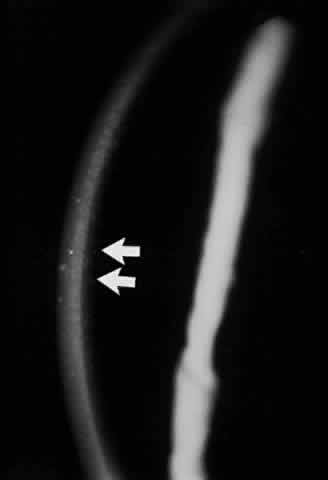

Conjunctival involvement in epidermolysis bullosa begins with vesicle formation, leading to ulceration and symblepharon formation.107 In the cornea, recurrent erosions occur that lead to vascularized scars (Fig. 18). Histologically, the epithelium exhibits vacuolation, particularly of the basal cell layer. The epithelium is poorly adherent to Bowman's membrane, whereas the remainder of the corneal structure is essentially normal.108 McDonnell reported that 8 of 11 patients with the dystrophic form of epidermolysis bullosa had ocular abnormalities, including conjunctival shrinkage, with symblepharon formation and corneal opacities.109 The authors remarked that these abnormalities were slowly progressive, and that except for recurrent corneal erosion, the patients were ocularly asymptomatic. Other ocular histopathologic changes have been noted in epidermolysis bullosa letalis by Aurora and co-workers.110 They have described a patient exhibiting edema of the trabeculum, iris, ciliary body, lens, and optic nerve. Focal edema and necrosis of the choroid and retina as well as total retinal detachment were also present in this patient. Citing research by other workers, these authors suggest that some of the ocular changes observed in epidermolysis bullosa may be due to focal accumulation of a proteolytic enzyme, possibly collagenase. Zierhut and associates, using modern criteria for the definitive diagnosis of epidermolysis bullosa acquisita (EBA), reported the case history of a 23-year-old man with EBA who developed bilateral tiny corneal subepithelial vesicles.111